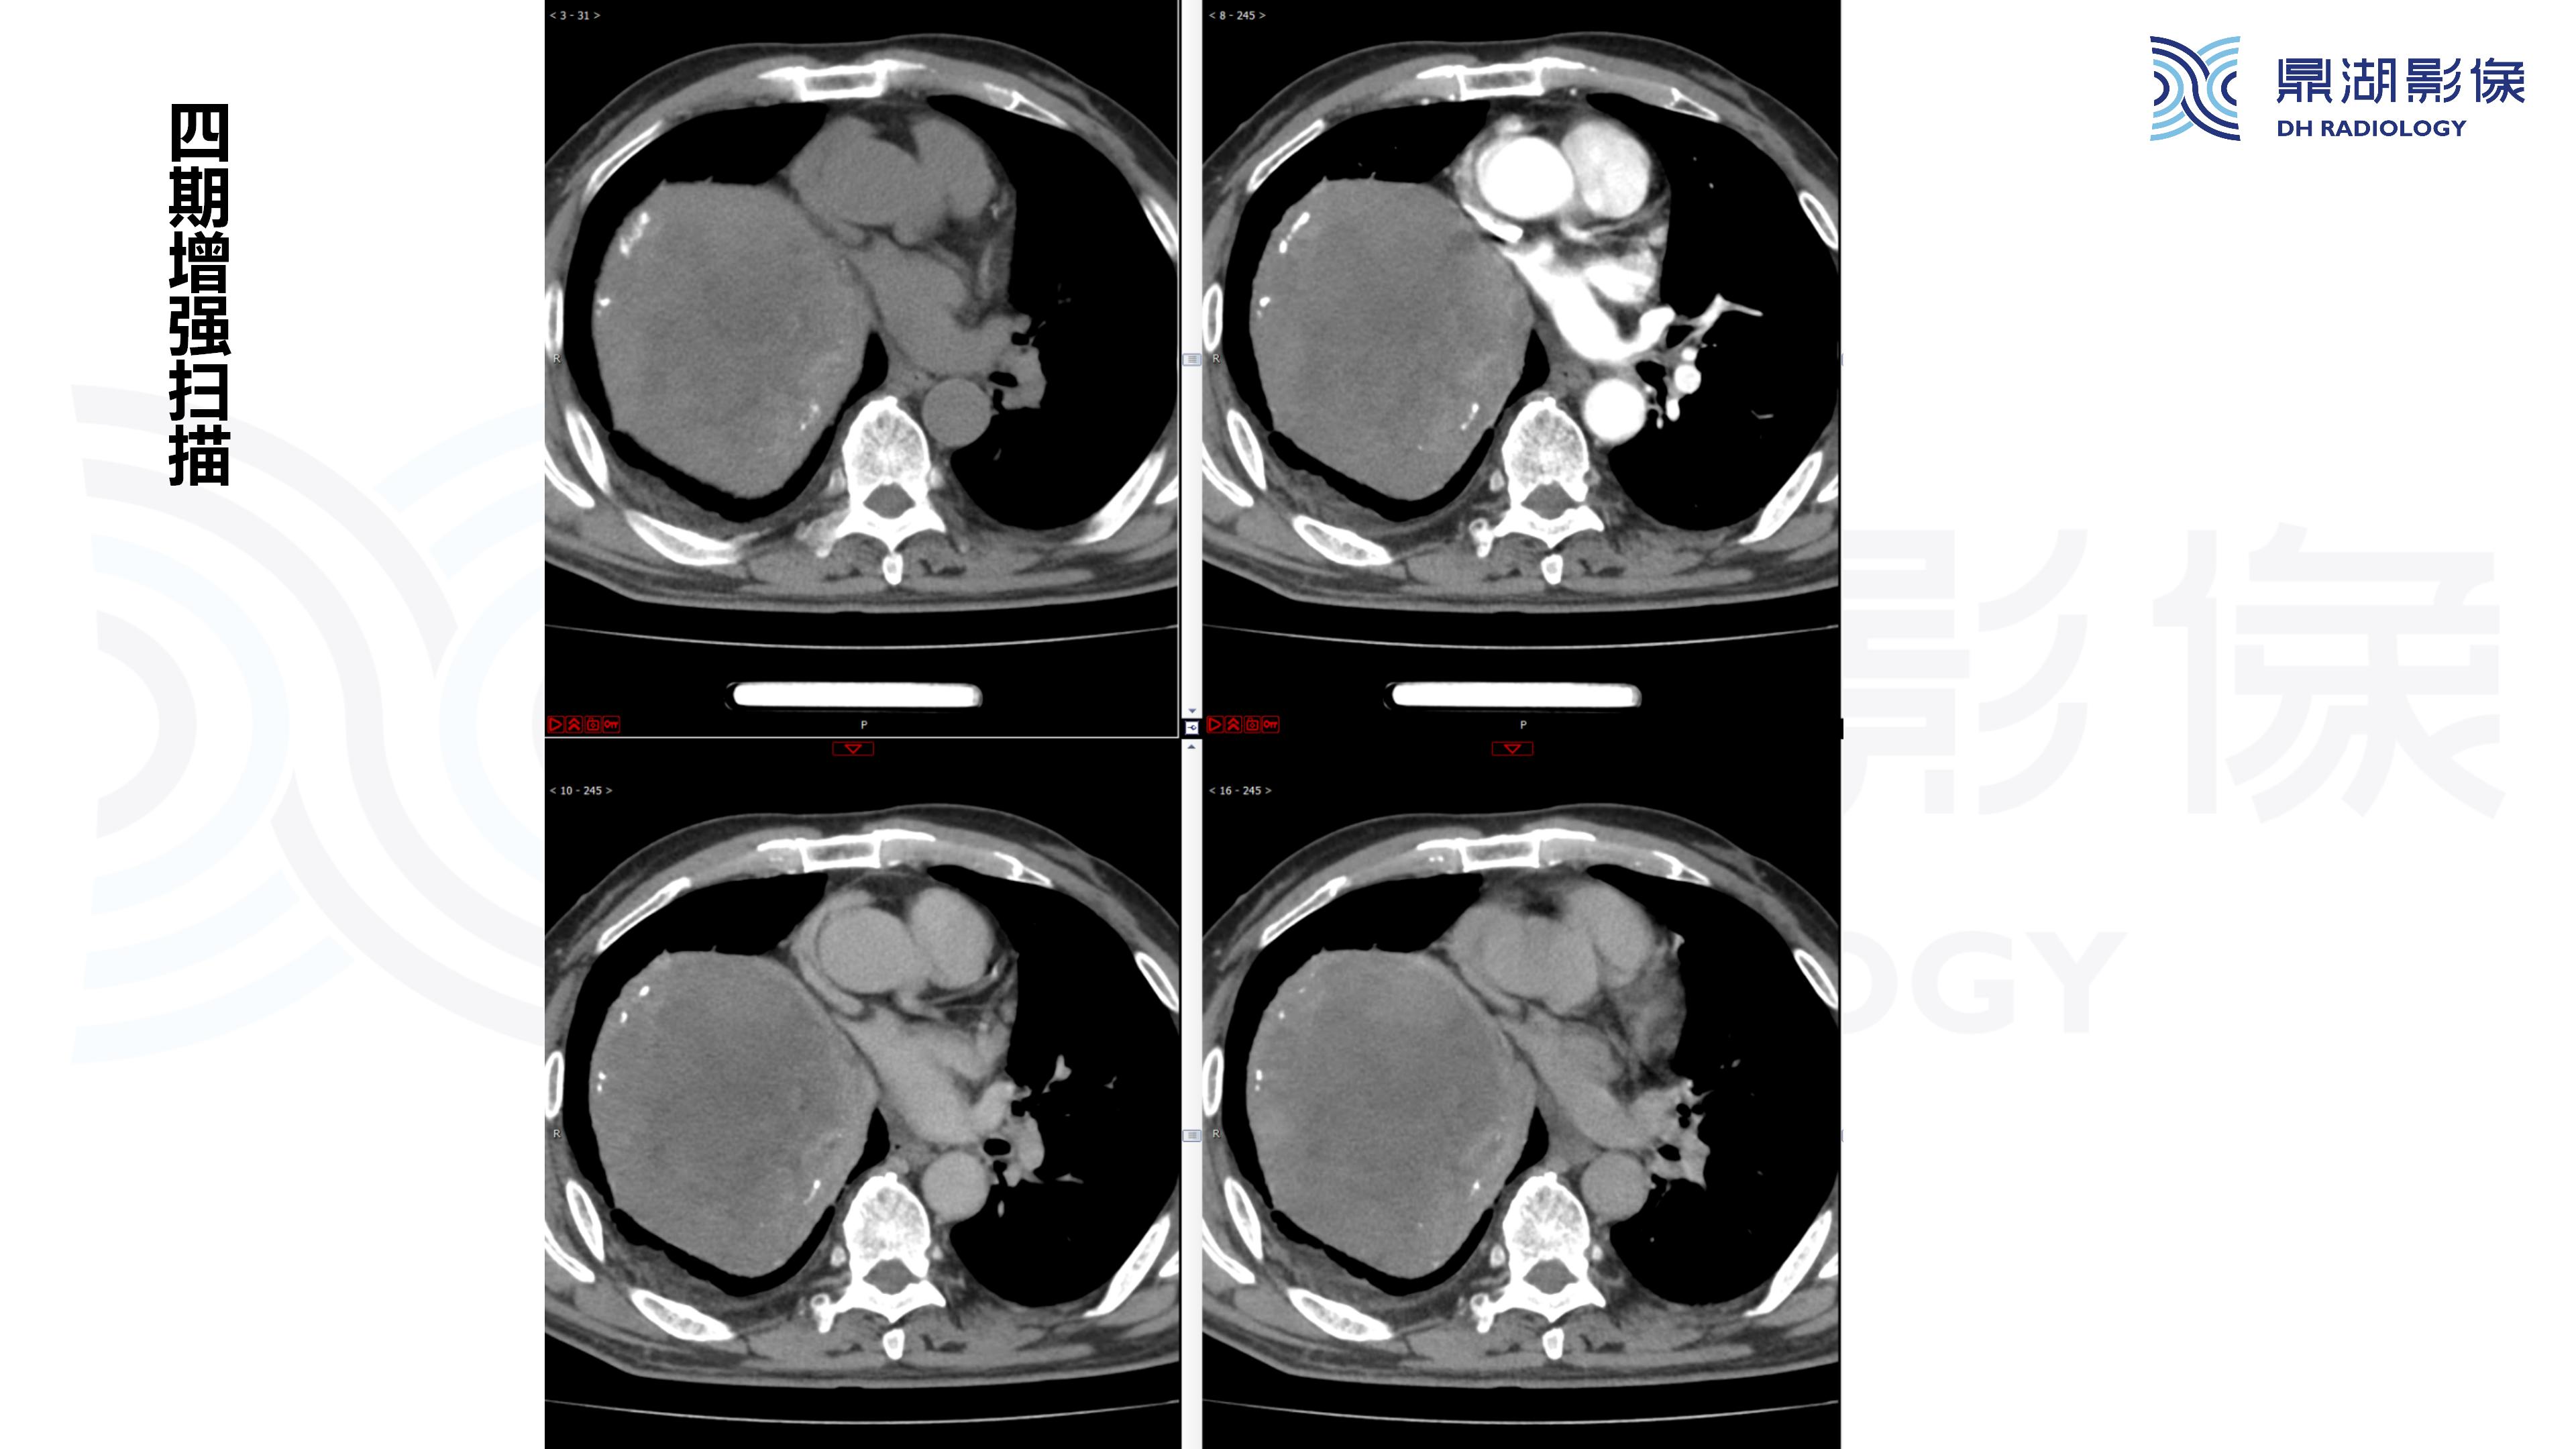

纵隔血管瘤-鼎湖社群读片病例